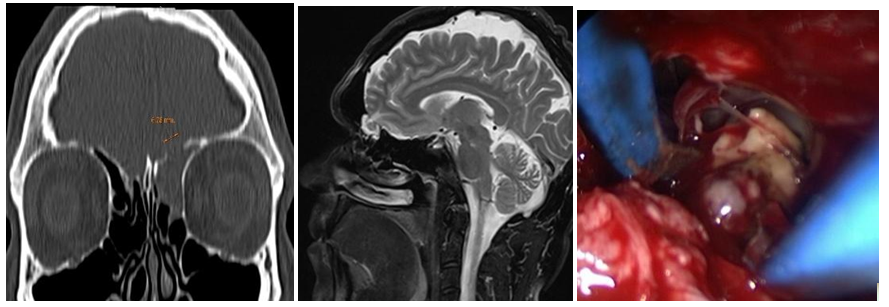

Figure 6A-B Frontal Sinus MEC. C: DRAFIII Surgery. D: Herniated brain tissue bipolar cauterization. E: Multilayer reconstruction with autologous cartilage and nasoseptal flap.

Intranasal MC was the most frequent lesion (6/5) and there was one patient with MEC (1/6). Five cases were idiopathic and one patient had history of transnasal surgery for a tumor of the sellar region and sphenoid plane 15 days before. 83,3% of the cases were primary surgeries and one patient had 3 prior MC surgeries. In 2 cases the MC was located in the sphenoid lateral wall (Figures 1A-B), one was located in the sphenoid roof (Figure 2), 2 in the cribriform plate and one patient, with MEC diagnosis, had it located in the frontal sinus. 66,6% had anterior rhinorrhoea (4/6) (Table 1). All patients were studied before surgery, only in four of them (66,6%) the lesion location was detected by at least one of the studies (CT, MRI and/or endoscopy). For one patient with MC of the lateral sphenoid wall intrathecal fluorescein was used prior to surgery (10cc of CSF were extracted by lumbar puncture and mixed with 0.2ml of 5% fluorescein, then 1ml per minute was delivered by intrathecal injection. We performed a multilayer closure technique in all patients (Figures 3A-C). In 4 cases we used autologous fat with mucoperichondrium (Figures 4A-B) and (Figures 5A-C) and in 2 cases autologous cartilage with mucoperichondrium. We used an intranasal transpterygoid approach for one case of lateral sphenoid wall mucocele, a Draf III technique in une case of frontal sinus MEC (Figures 6A-E). During the immediate postoperative period, one patient had acute meningitis that resolved with intravenous empirical antibiotics. One patient had a CSF leak recurrence 4 months after surgery. He was treated by external approach and had no relapse. No complications during postoperative follow up. The success rate of the reconstructions performed by endonasal approach was 83.33% (5/6). The average follow-up of the patients was 15 months.